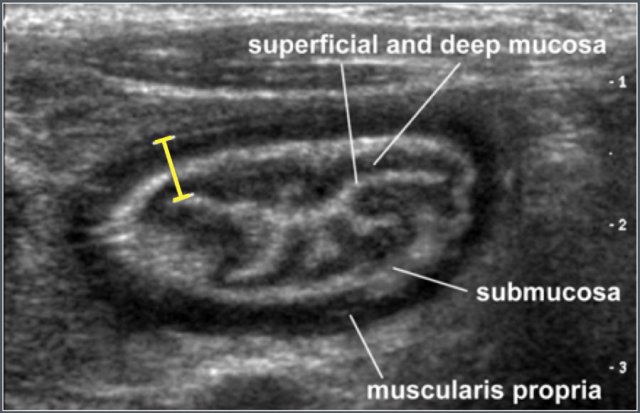

Bowel wall thickness was measured on transverse sections and comprised of mucosa, lamina propria, muscularis mucosa, submucosa, and muscularis propria.

Ultrasonographic measurement of wall thickness of terminal ileum in a 12-year-old boy with cystic fibrosis.